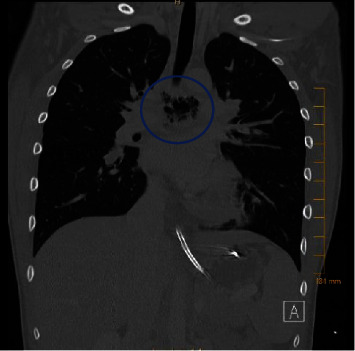

Streptococcus intermedius is an inhabitant of the oral cavity and gastrointestinal tract, known to cause deep-seated abscesses. Thereby, we present a previously healthy adolescent with esophageal perforation (EP) and secondary mediastinal and brain abscesses due to Streptococcus intermedius. EP is a potentially life-threatening condition that requires a prompt diagnosis.